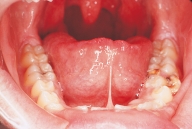

Introduction to Preliminary Diagnosis of Oral Lesions